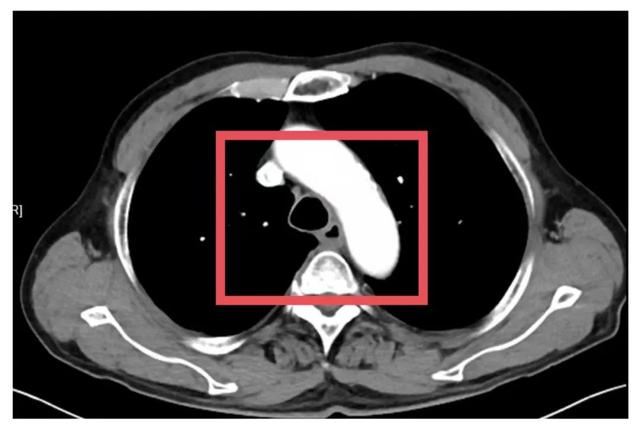

▲患者术前、术后影像对比

为了争取更大的根治机会,胸外科朱震主任医师为苏先生量身定制定了一套治疗方案——“免疫联合化疗”的新辅助治疗方案,先“软化”肿瘤、减少侵犯,再择期手术。治疗期间,苏先生接受了PD-1单抗与铂类+紫杉醇联合化疗。随着治疗推进,患者主诉症状显著缓解。2025年7月复查CT提示病灶缩小、边界清晰、与周围结构粘连减少,手术时机成熟。

术后,苏先生康复进展顺利,未出现肺部感染、吻合口瘘等并发症。最令人振奋的是,术后病理结果提示:肿瘤区域未见残留癌细胞,达到“病理完全缓解(pCR)”标准!这意味着,新辅助治疗获得高度成功,同时也为患者带来更佳的长期预后!